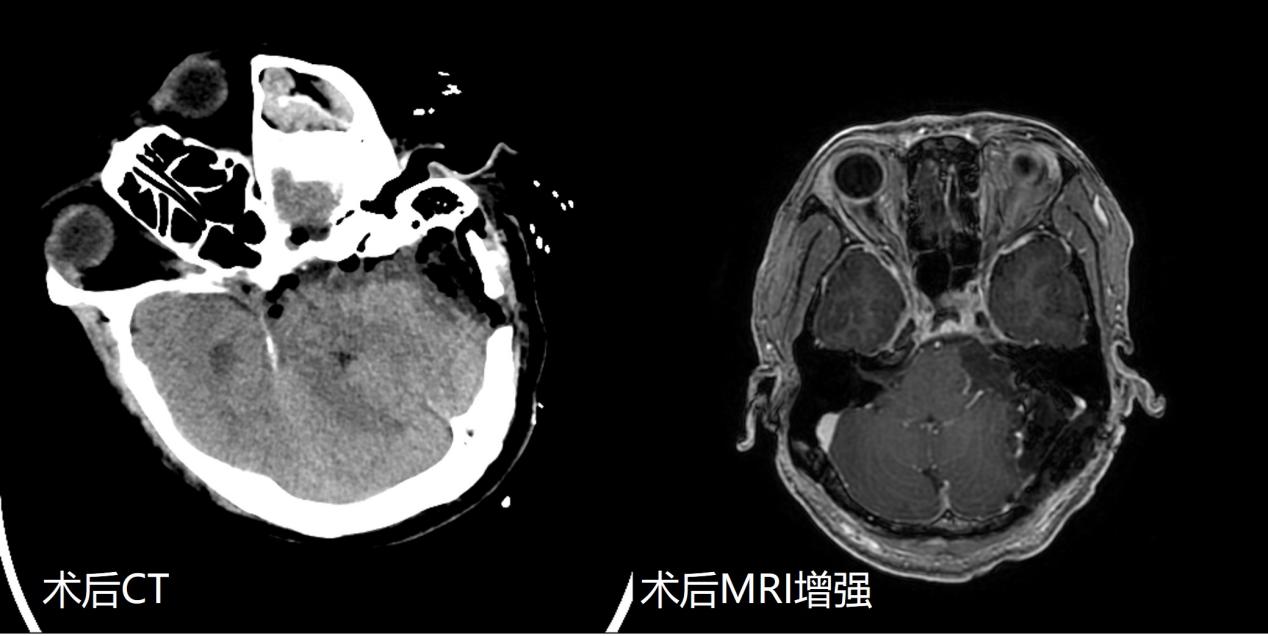

入院后,神经外科周乐教授、权俊杰副教授、马程文博士精心准备。在神经电生理监测技术辅助下,应用显微镜下神经束膜下分离技术,将肿瘤完全剥离切除,面听神经得到解剖保留。术后影像检查证实肿瘤完全切除。术后患者面部肌肉运动正常,同侧听力虽有下降,但仍有功能。目前患者已康复出院。

此次手术为我院首次听神经瘤全切+面神经保留+听神经保留手术,代表着我院在听神经瘤手术领域达到国内先进水平。